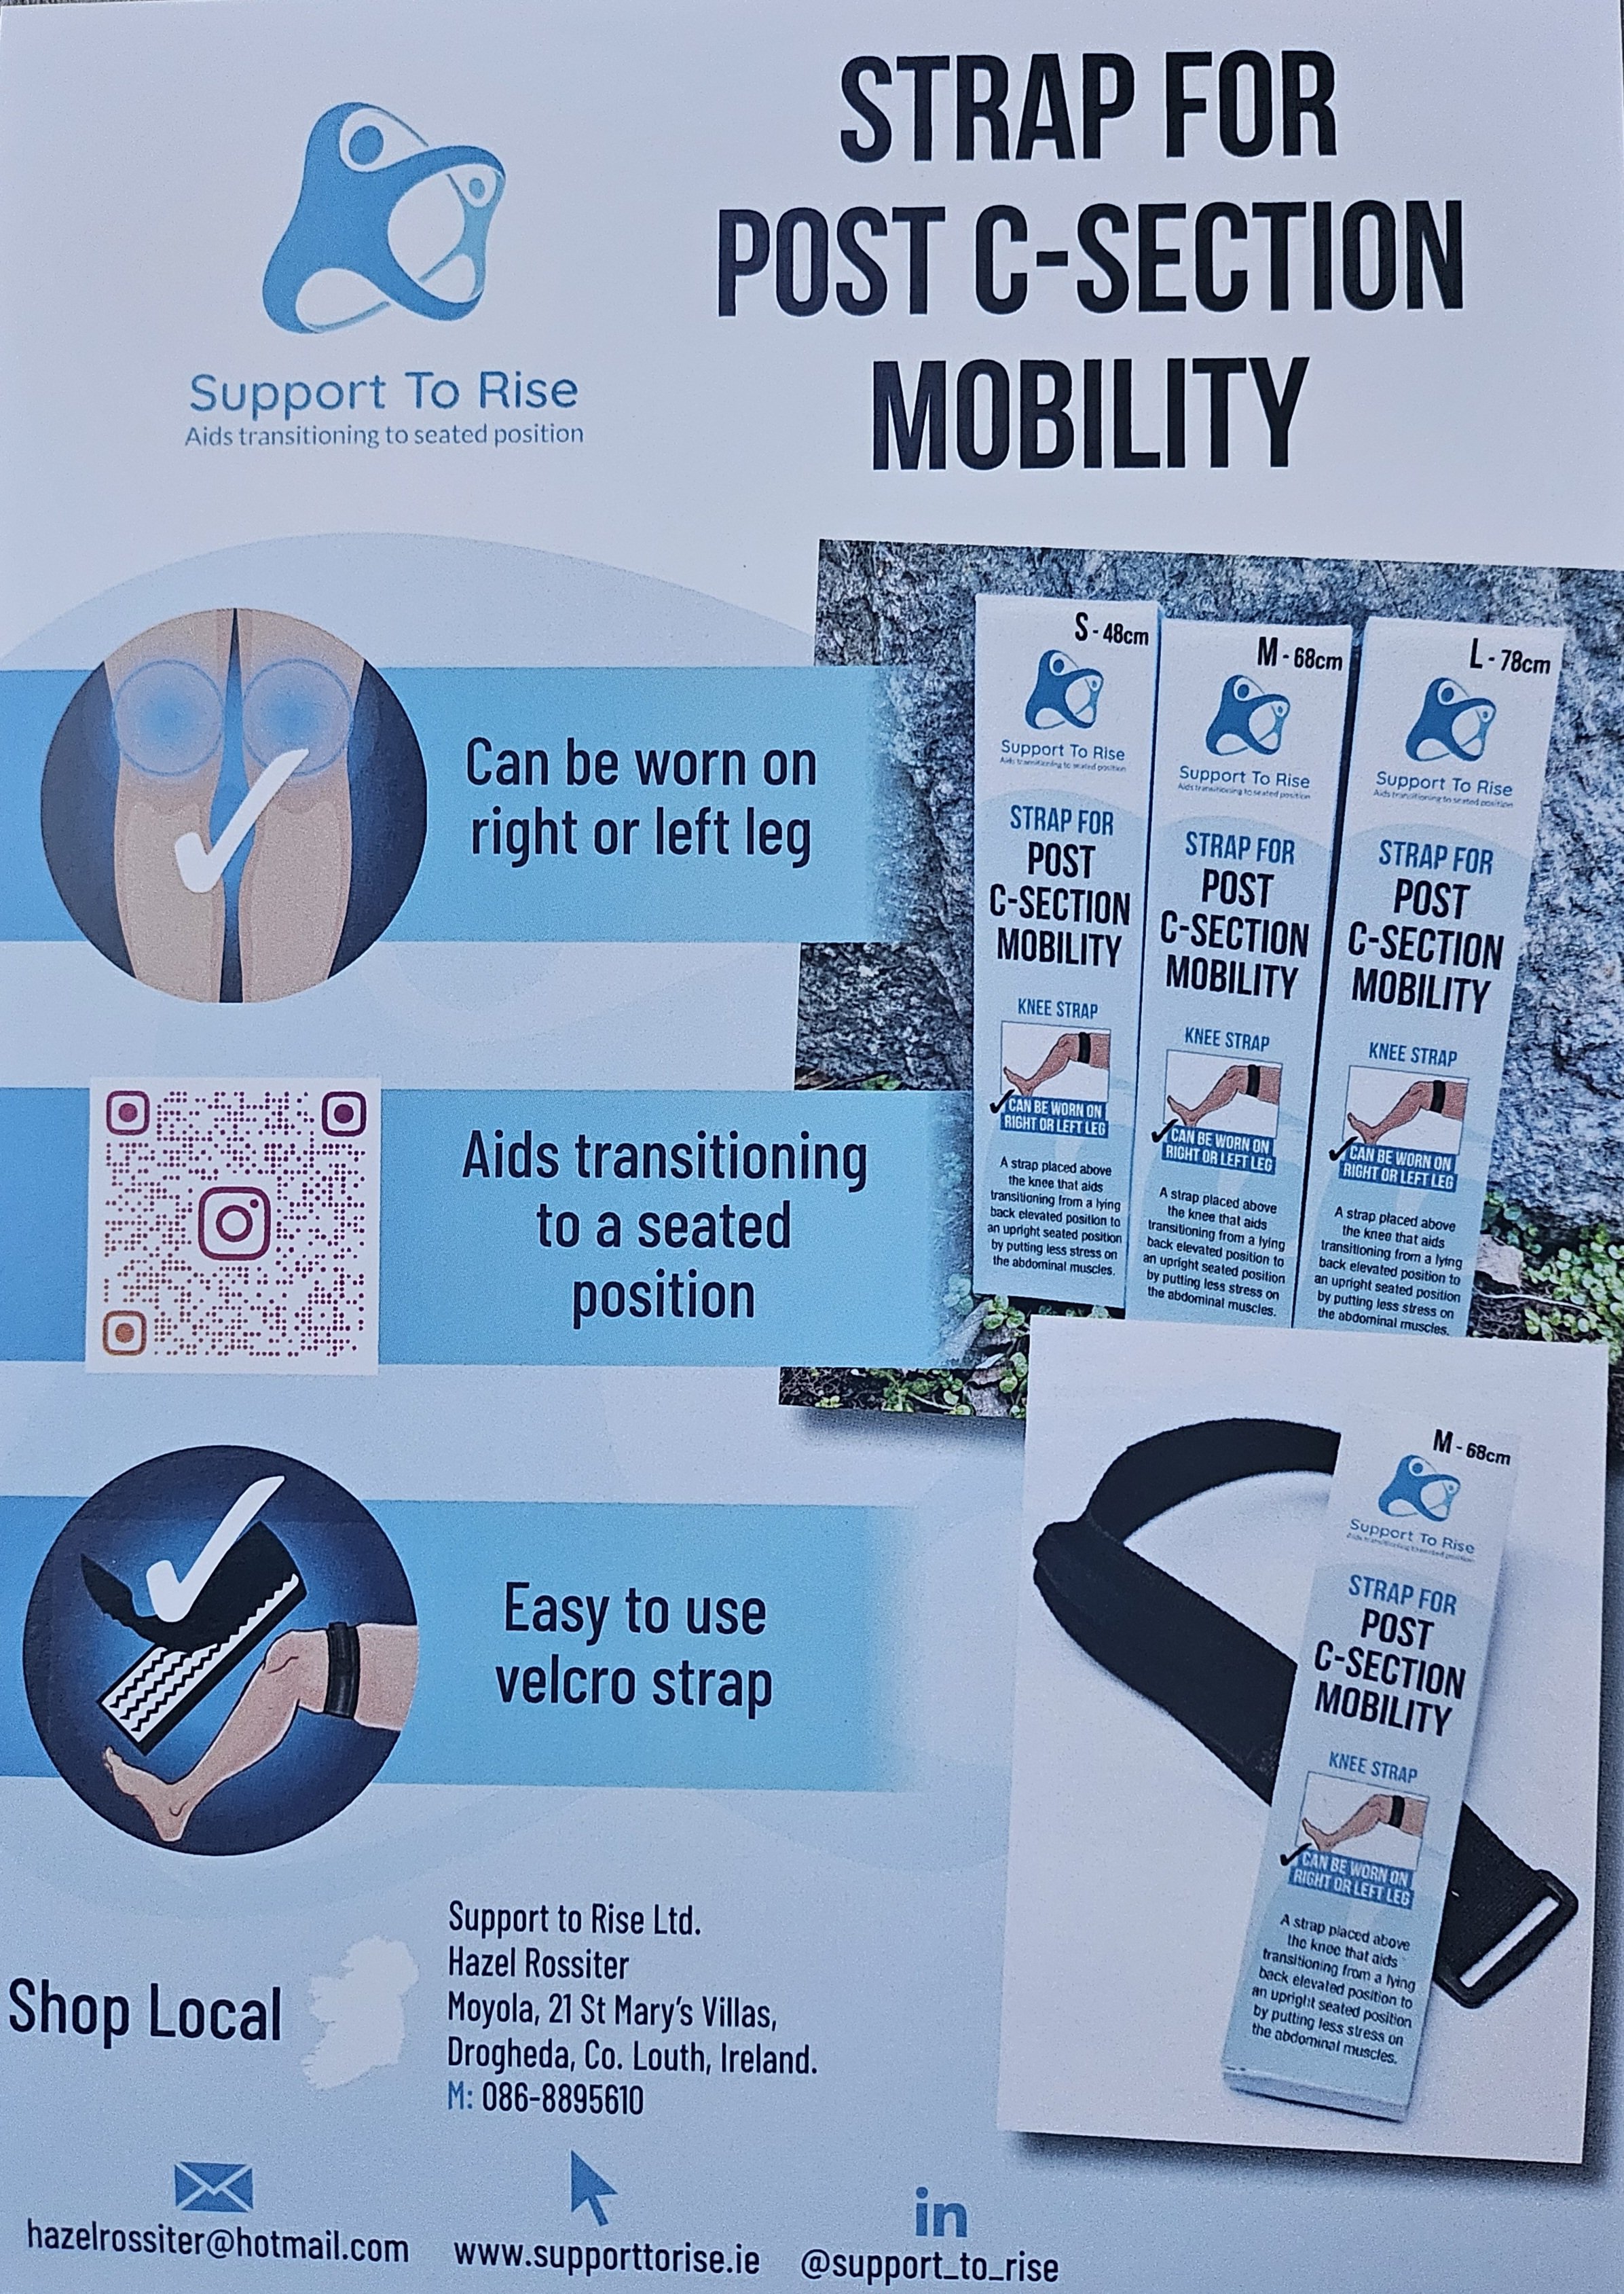

Indulge in optimal post C-section surgery comfort with our meticulously crafted Strap. Strategically designed to provide support, our innovative strap ensures a seamless transition during the crucial stages of recovery. Engineered for versatility, it effortlessly adapts to both right and left legs, accommodating individual preferences. The incorporated handle not only guarantees a secure grip but also facilitates controlled movements, promoting a confident rise with each use. The adjustable Velcro closure adds a layer of personalized comfort, while the carefully selected materials—durable polyester tape, supportive rubber foam, and a reliable buckle—underscore our commitment to quality.

Increased Mobility: The Strap helps to improve your mobility, to help you rise up out of bed with less pressure to the abd which is important after major abdominal surgery such as a caesarean section or hysterectomy.

Enhanced Stability: The Strap ensures stability during movements, featuring a strategically placed handle and an adjustable Velcro closure. This design provides users with confidence during transitions, minimizing the risk of strain on abdominal muscles.

Reduced Abdominal Strain: With a secure grip handle, our Knee Strap empowers users to rely on arm strength, minimizing strain on abdominal muscles. This innovative approach not only aids in a smoother recovery process but also minimizes discomfort associated with traditional movements.

Instructions For Use:

Wrap the strap around the leg just above the knee. Make sure the handle is facing upwards. Tighten using the velcro close. Place your fingers through the handle. Use the strength in your arms to pull yourself upwards. By using the strength in your arms, you avoid using abdominal muscles.